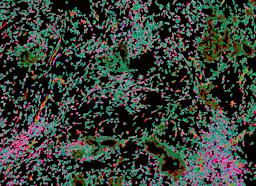

Pancreatic ductal adenocarcinoma is a lethal disease with limited treatment options and poor survival. We studied 83 spatial samples from 31 patients (11 treatment-naïve and 20 treated) using single-cell/nucleus RNA sequencing, bulk-proteogenomics, spatial transcriptomics and cellular imaging. Subpopulations of tumor cells exhibited signatures of proliferation, KRAS signaling, cell stress and epithelial-to-mesenchymal transition. Mapping mutations and copy number events distinguished tumor populations from normal and transitional cells, including acinar-to-ductal metaplasia and pancreatic intraepithelial neoplasia. Pathology-assisted deconvolution of spatial transcriptomic data identified tumor and transitional subpopulations with distinct histological features. We showed coordinated expression of TIGIT in exhausted and regulatory T cells and Nectin in tumor cells. Chemo-resistant samples contain a threefold enrichment of inflammatory cancer-associated fibroblasts that upregulate metallothioneins. Our study reveals a deeper understanding of the intricate substructure of pancreatic ductal adenocarcinoma tumors that could help improve therapy for patients with this disease.